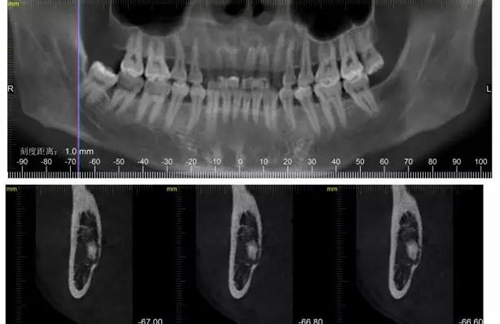

下面CBCT,可以看到兩個(gè)牙根的根尖三分之一在神經(jīng)管里面。

1500632963_511898.jpg